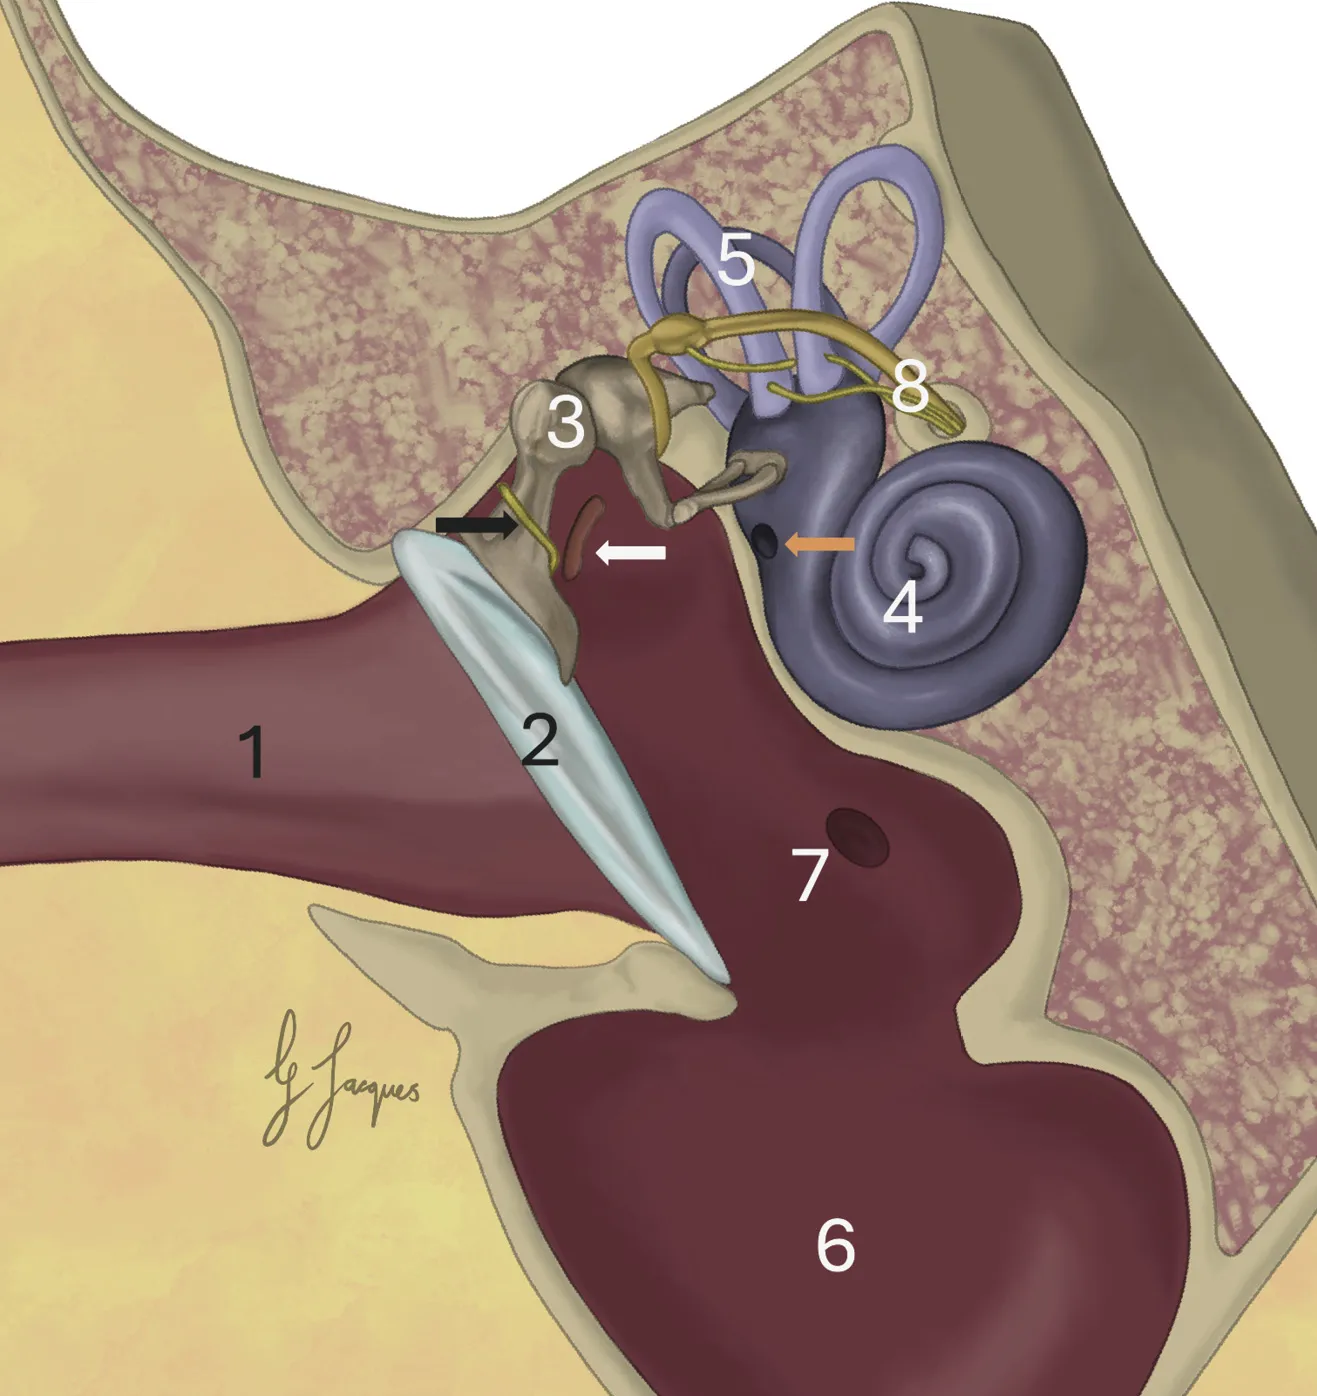

El oído medio es una cavidad situada entre el oído externo y el interno, limitada lateralmente por la membrana timpánica y medialmente por las ventanas coclear y vestibular, que comunican con el laberinto óseo donde se encuentran la cóclea y los canales semicirculares.

La membrana timpánica consta de dos secciones: la pars flaccida (más pequeña) dorsalmente y la pars tensa (más grande) ventralmente. En la superficie medial de la pars tensa se inserta el manubrio del hueso martillo, que se visualiza externamente como la estría del martillo (estria mallearis) (imagen 1).

La cavidad timpánica está alojada en la bulla timpánica (imagen 2). Su mucosa, de epitelio escamoso simple, recibe inervación del plexo timpánico, principalmente derivado del nervio glosofaríngeo. Consta de un pequeño receso epitimpánico dorsal, la cavidad timpánica propiamente dicha y la cavidad ventral. Ambas estructuras están separadas por una cresta ósea (bulla del tabique), que es incompleta en el perro, pero en los gatos separa casi por completo la cavidad en dos compartimentos (dorsolateral y ventromedial).

En el interior del oído medio se encuentran los tres huesecillos auditivos: martillo, yunque y estribo, que forman una cadena articular que transmite las vibraciones de la membrana timpánica hasta la ventana vestibular. Sus movimientos están regulados por dos músculos diminutos, el tensor del tímpano y el estapedio, cuya contracción protege al oído interno frente a estímulos sonoros intensos o repetitivos.

En la porción rostral de la cavidad timpánica se inicia la trompa auditiva (o de Eustaquio), que conecta la cavidad timpánica con la nasofaringe. Está tapizada por epitelio respiratorio ciliado con células caliciformes y su apertura se mantiene gracias a la acción coordinada de los músculos tensor y elevador del velo del paladar, inervados por ramas de los nervios trigémino y facial, respectivamente. El nervio facial ingresa al conducto auditivo interno y recorre un túnel óseo, el canal facial, del hueso temporal petroso. En los perros este canal está incompleto y parte del nervio facial está expuesto, por lo que una infección en el oído medio podría provocar parálisis facial. En los gatos, sin embargo, el canal facial está completo y no expone los nervios faciales a su paso por el oído medio, por lo que la parálisis facial asociada a otitis media es poco frecuente.

Una rama del nervio facial, la cuerda del tímpano, sale del canal facial, pasa por debajo de la base del martillo medialmente, cerca de la pars flaccida, y sale del oído medio para fusionarse con la rama lingual del V par craneal e inervar el tercio rostral de la lengua. Otra rama del nervio facial, el nervio petroso mayor, proporciona inervación a las glándulas lagrimales y nasales laterales. Las fibras posganglionares del tronco simpático cervical se encuentran en la pared dorsomedial de la cavidad timpánica. En los perros, estas recorren el hueso temporal petroso asociado con la arteria carótida interna en el canal carotídeo. Sin embargo, los gatos no tienen un canal carotídeo y las fibras nerviosas simpáticas entran en la cavidad timpánica y forman un plexo que recubre el promontorio coclear.

En el oído interno se alojan la cóclea y los canales semicirculares. La cóclea es una estructura del oído interno relacionada con la audición mediante el nervio coclear. Los canales semicirculares conforman otra parte del oído interno y están vinculados al sentido del equilibrio a través del nervio vestibular. Ambas estructuras, la cóclea y los canales semicirculares, contienen líquido que se desplaza por el movimiento en las ventanas vestibulares. Este desplazamiento activa los estereocilios especializados presentes en cada estructura, estimulando las terminaciones nerviosas de los nervios coclear y vestibular, respectivamente.